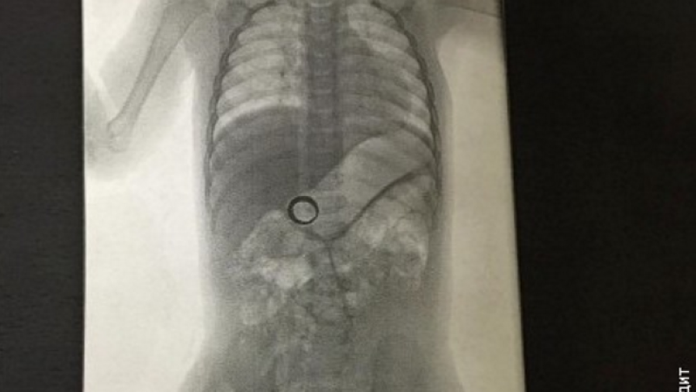

Röntgen žalúdka 14-mesačného chlapčeka

Zlodeja potvrdila až snímka žalúdka.

Žena zo Seattlu zostala zaskočená, keď svoj svadobný prsteň nenašla na mieste, kde si ho vždy odkladala. Najskôr začala hľadať v celom dome, no keď prsteň nenašla ani tam, jej manželovi napadlo ešte jedno miesto, kde by sa prsteň mohol nachádzať. Keďže ich 14-mesačné dieťa im toho ešte veľa prezradiť nemohlo, zobrali ho do nemocnice, píše CNN.

Tam mu urobili röntgen žalúdku. To čo videli na snímke u nich na jednej strane vyvolalo radosť, že prsteň našli, no na druhej strane strach z toho, ako prsteň z detského bruška dostať. Dieťa zostalo na pozorovaní 8 hodín a nakoniec ho poslali domov. Rodičom dali úlohu, aby počas dvoch týždňov sledovali každú stolicu svojho dieťaťa, pretože prsteň by mal vyjsť von prirodzeným spôsobom. Tiež ich však upozornili na to, že ak sa tak do dvoch týždňov nestane, vyberú prsteň zo žalúdka operačne.